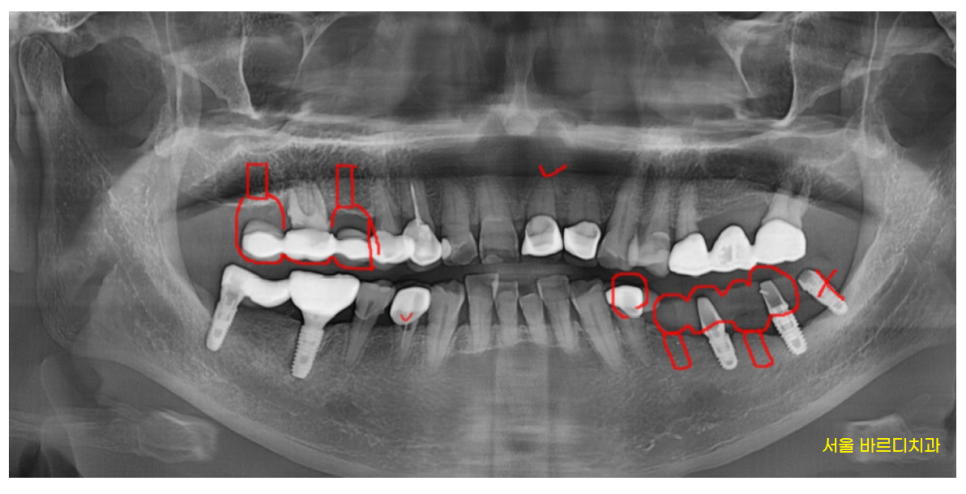

환자분은 왼쪽 아래 오래전에 한 임플란트가

들썩 들썩 흔들려서

식사를 못하고 계신다 하셨습니다.

23.08.23

망월동 치과에서 발치후

왼쪽 아래 임플란트 먼저 수술하였습니다.

재수술인셈이죠.

기존에 있는 임플란트를 제거 후

교체해주는 작업을 진행하였습니다.

오른쪽 위 보철이 빠지셨답니다..!!

이런 경우가 굉장히 많습니다.

임플란트 반대편 치아가 문제가 생기는 경우요.